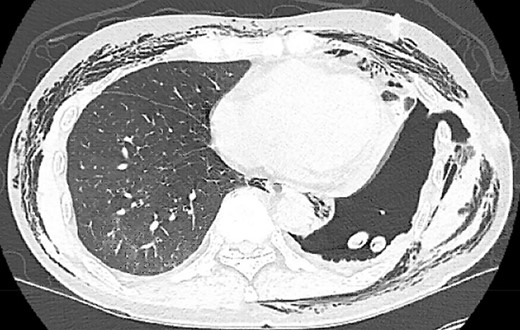

Once the pleural space infection was eradicated, he underwent definitive BPF closure with a left vertical rectus abdominis myocutaneous (VRAM) free flap alongside Plastic Surgery, 11 months after his first operation. The muscular portion of the flap was secured over the BPF with Vicryl suture, and the skin paddle was used to close the chest-wall. The night of POD 0, he developed subcutaneous emphysema, swelling and flap compromise. He underwent exploration with hematoma evacuation from the subcutaneous space, improving flap perfusion. Two 24 Fr. Blake drains were placed, and the patient was discharged uneventfully. The drains were later removed, and the patient is doing well without respiratory, infectious or BPF issues (Fig. 4).

(A) POD 0 status post VRAM flap. (B) POD1 status post take back. (C) About 3 months post VRAM flap.